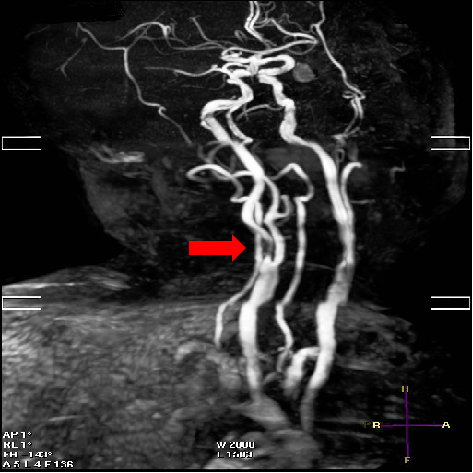

颅脑磁共振+头颈MRA:未见新发梗死;右侧颈内动脉C1段重度狭窄。